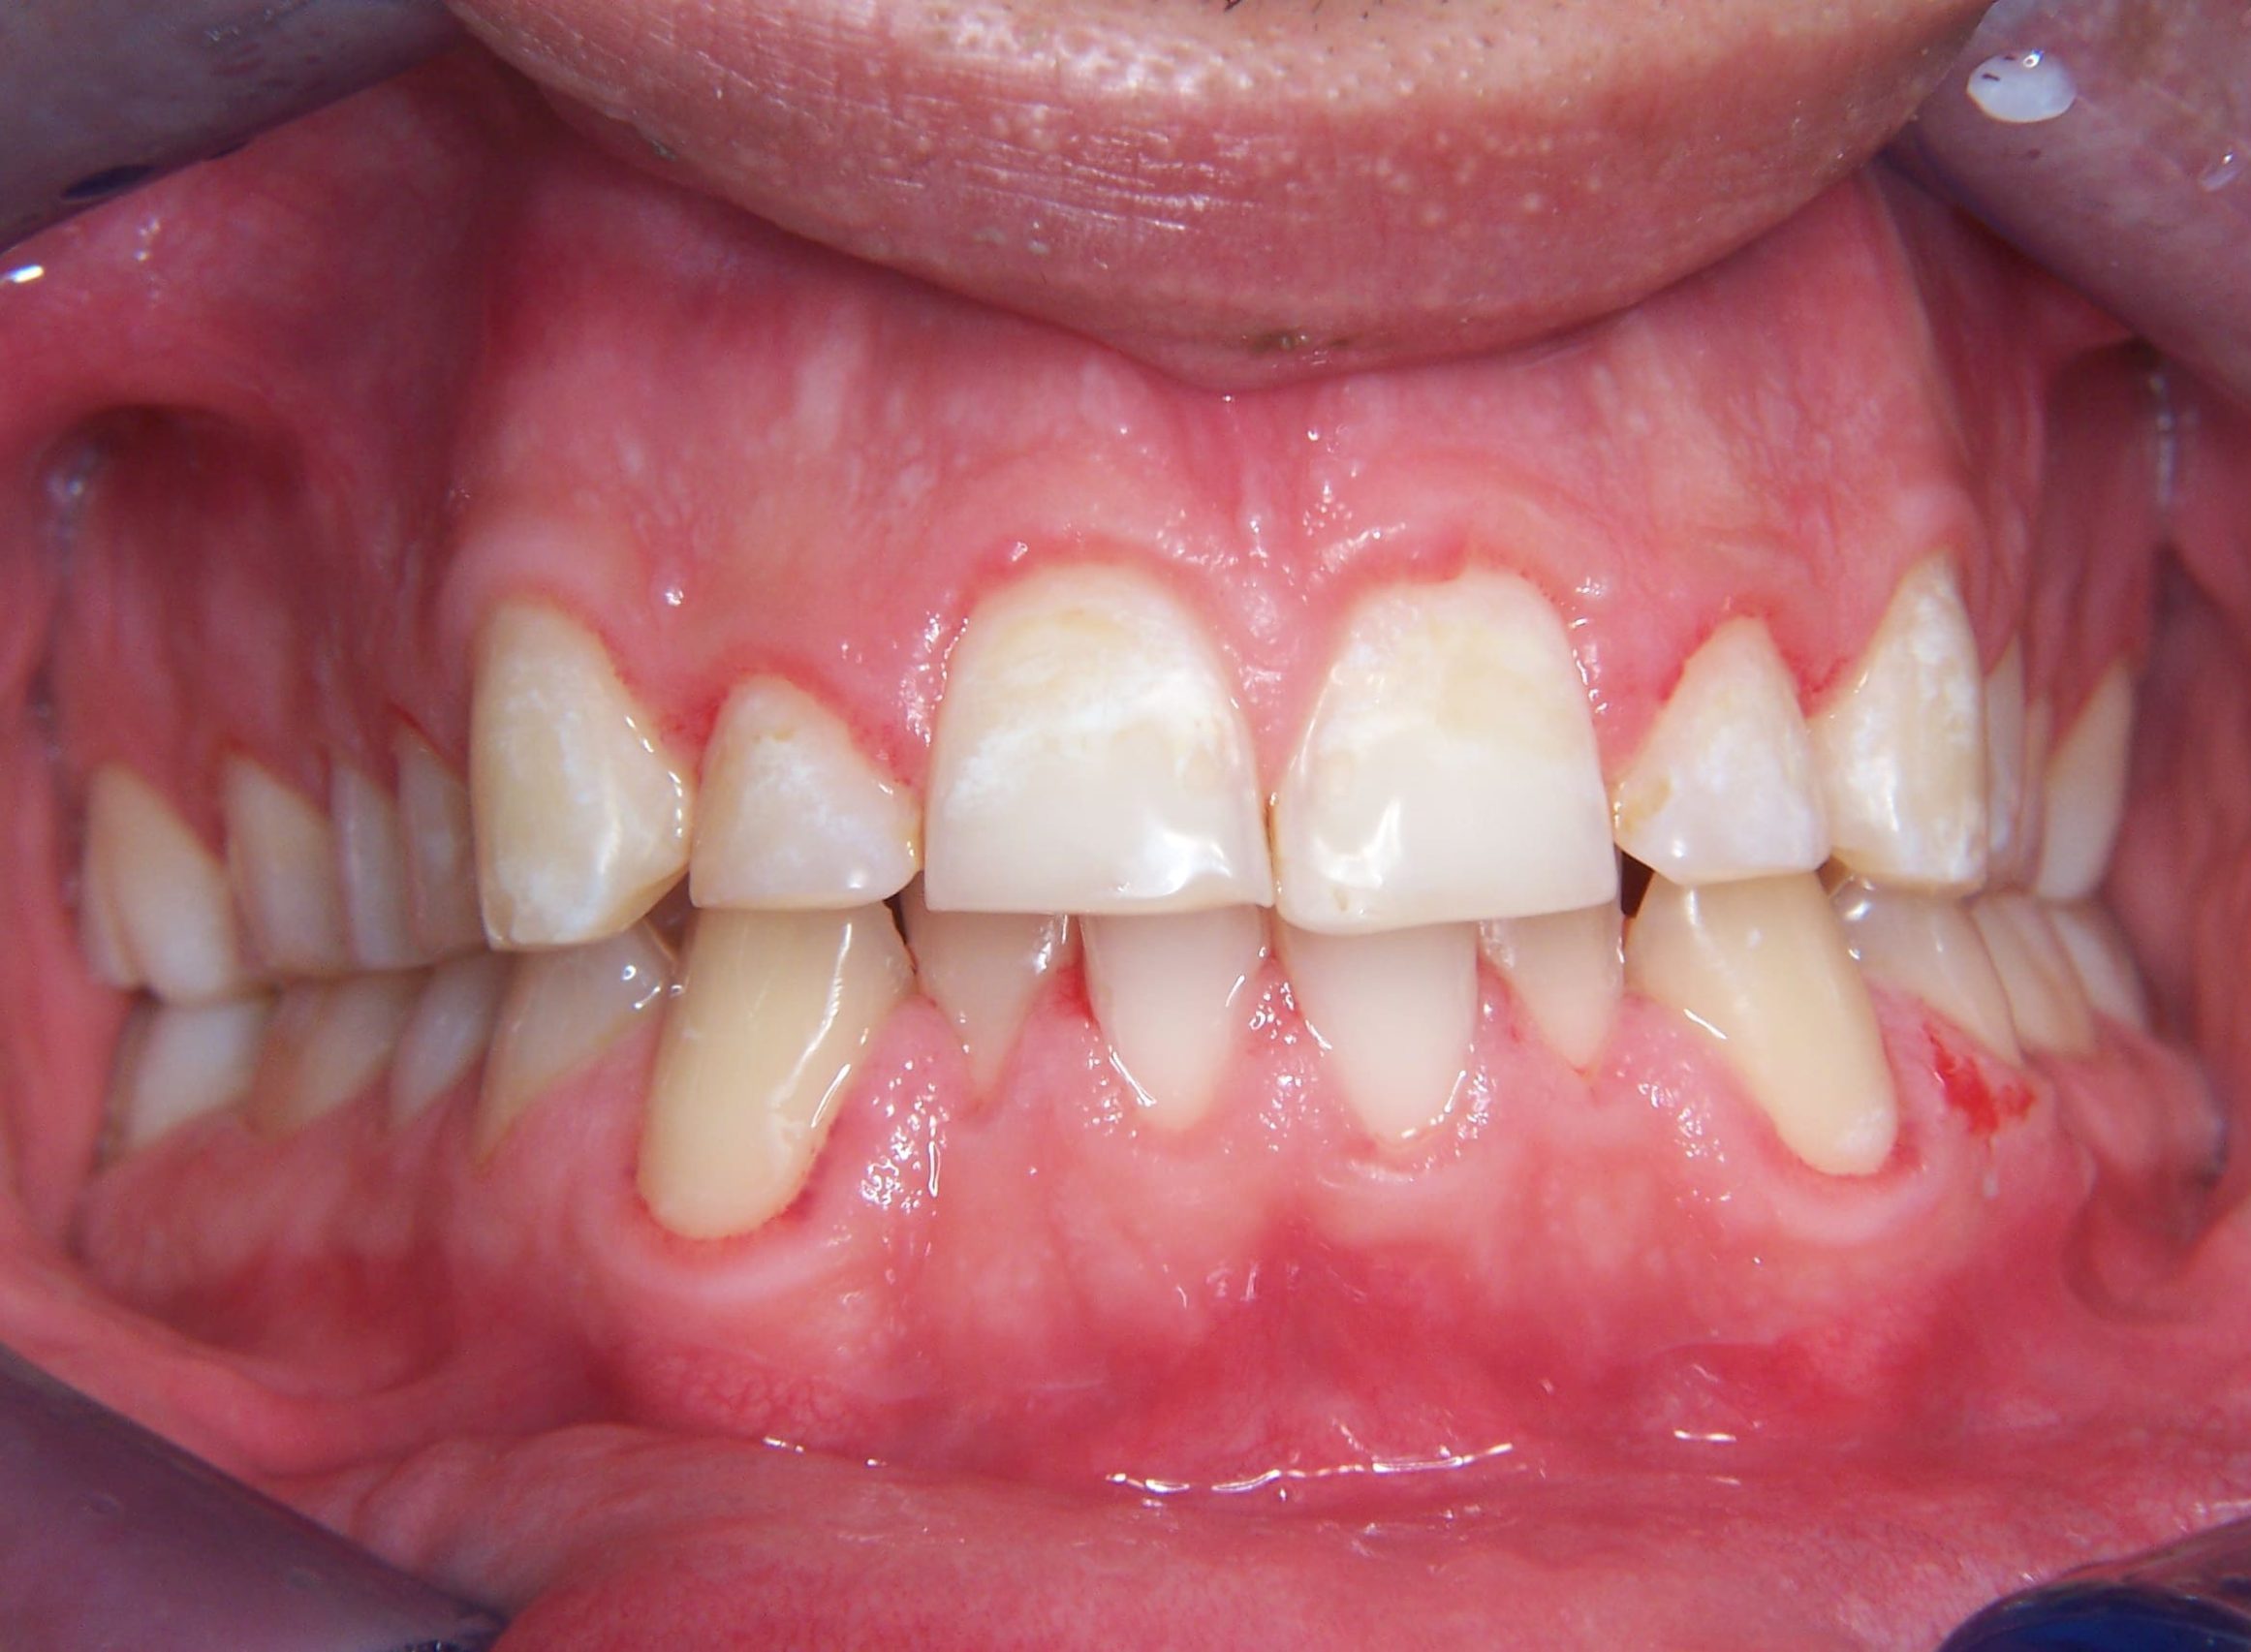

Prima

Dopo